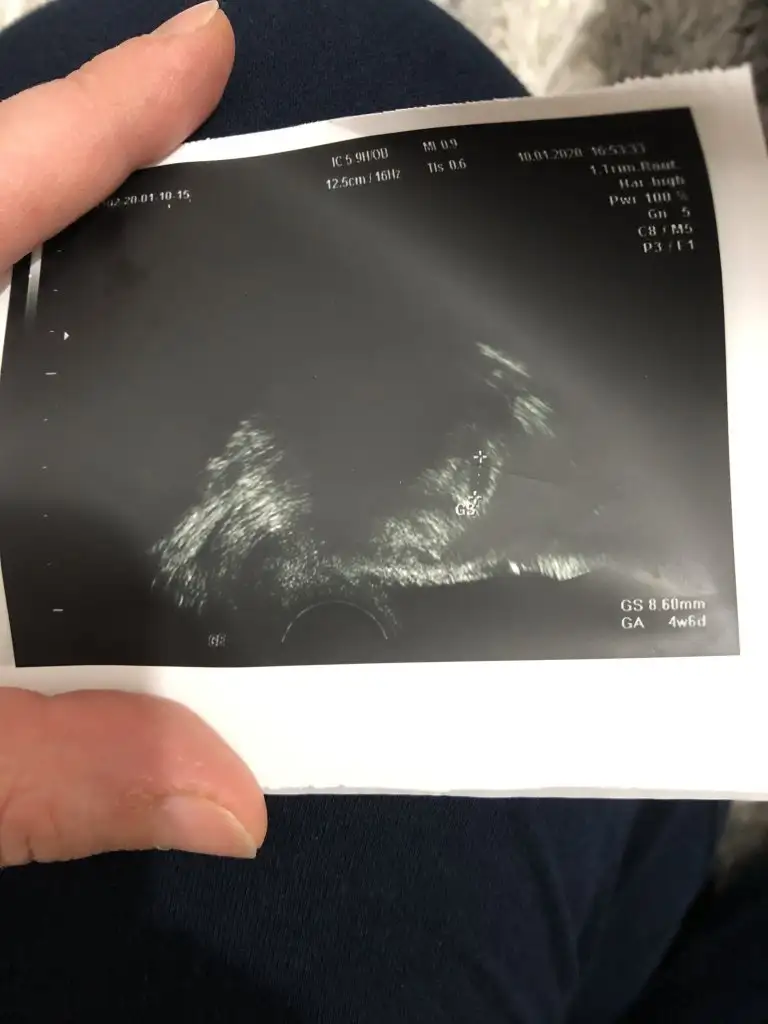

kese vardı yanlış yazmisim4+5 te bende gittiğimde bebek yoktu kese yoktu dr bakmadan görünmeyebilir haberin olsun dedi. Ama allaha şükür inşallah hepimizin kucagimiza alacağı kuzucuklari olsun. Sağlıkla gelsinler.